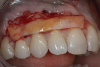

The graft is undermined by making an incision into the connective tissue layer using a #15C scalpel, leaving the epithelial layer intact (Figure 2). The tissue can then be lifted away and freed from the palate (Figure 3), after which it can be trimmed as necessary and ultimately transplanted back to the patient. The palate is then covered with a positive-pressure stent worn by the patient continuously for 1 week postoperatively, except when cleaning the stent after eating. During the second week postoperatively, the patient wears the stent only when eating. The palate is expected to be fully healed after the second week and then no longer requires protection. Surgical dressing is placed on the graft recipient site to reduce postoperative discomfort and facilitate proper healing of the graft site.

Fig 3. View of the free gingival graft that was lifted away and freed from the palate and then trimmed.